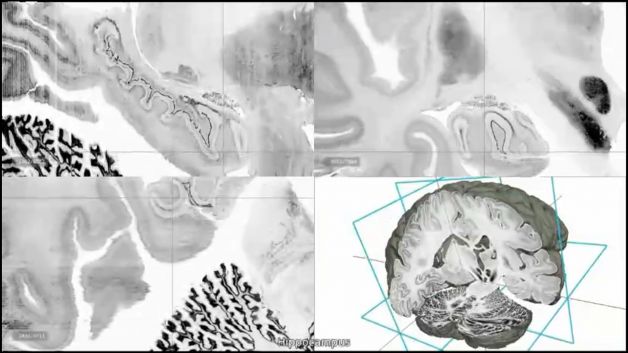

Tra i temi dell'esame di maturità, quest'anno spiccava il cervello. Negli stessi giorni, la rivista scientifica Science annunciava la realizzazione della prima mappa in 3 dimensioni di questo organo. Per ottenerla i ricercatori hanno sezionato il cervello di una donna deceduta, in più di 7 mila fettine di 20 micrometri di spessore. Questo risultato permetterà di studiare la forma e le funzioni del nostro cervello in modo estremamente approfondito. Le neuroscienze si confermano in questo momento la disciplina di maggior successo nel mondo scientifico e nell'interesse dei media.